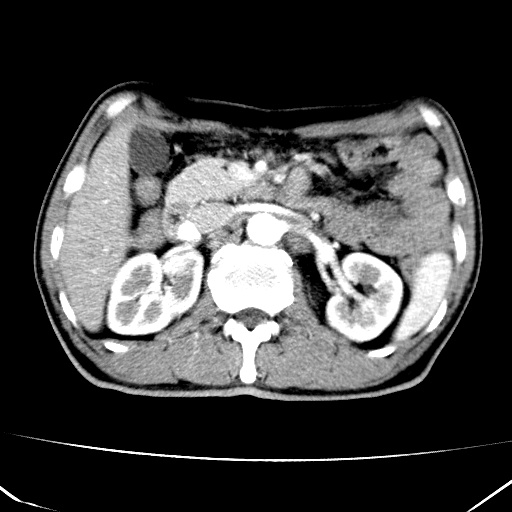

标题: CT17975:请求会诊。男、57岁。上腹部胀痛2天。临床诊断:糜 [打印本页]

标题: CT17975:请求会诊。男、57岁。上腹部胀痛2天。临床诊断:糜

考虑胃癌并肝脏及腹膜后淋巴结转移;不排除淋巴瘤。

肝内转移瘤,腹腔及腹膜后淋巴结转移。